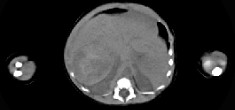

- 单项选择题男,刚刚出生5天, 上腹部膨隆,CT所见如图, 最可能的诊断为 ( )